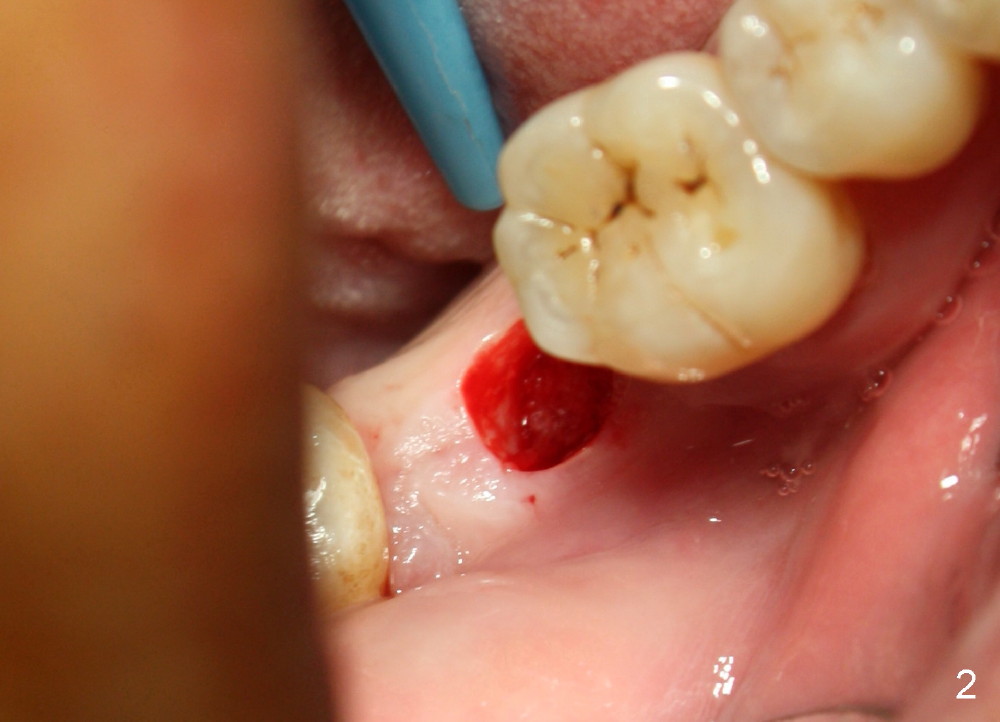

Luckily the patient returns for #31 implantation 4 months post socket preservation. Bone forms in the alveolus and above (Fig.1 black and white arrowheads, respectively). A 6 mm tissue punch is used to open the wound (Fig.2). Osteotomy forms using bone expanders, reamers and taps (Fig.3: 6x14 mm tap). Without infection, local anesthesia is more easily achieved than immediate implant when infection exists. The depth is controlled more readily with delayed implantation. Following adjustment of trajectory, a 7x11 mm implant is placed with insertion torque 60 Ncm (Fig.4 I). Fig.5 shows that the implant obliterates the wound; an abutment (A) is placed to retain perio dressing. With formation of new bone from socket preservation, insertion torque seems to be more easily obtained with the short implant. There is no space to re-use the harvested bone (Fig.6). The implant remains stable postop. Apparent new bone is forming toward the distal coronal threads 5 months postop (Fig.7). The bone around the implant remains stable 17 months post cementation (Fig.8), although there is an episode infection at the neighboring tooth (#30). The patient is more eager to have implants for the maxilla, since the flipper has lost. After implant placement at #7, the pain at #30 becomes more severe.